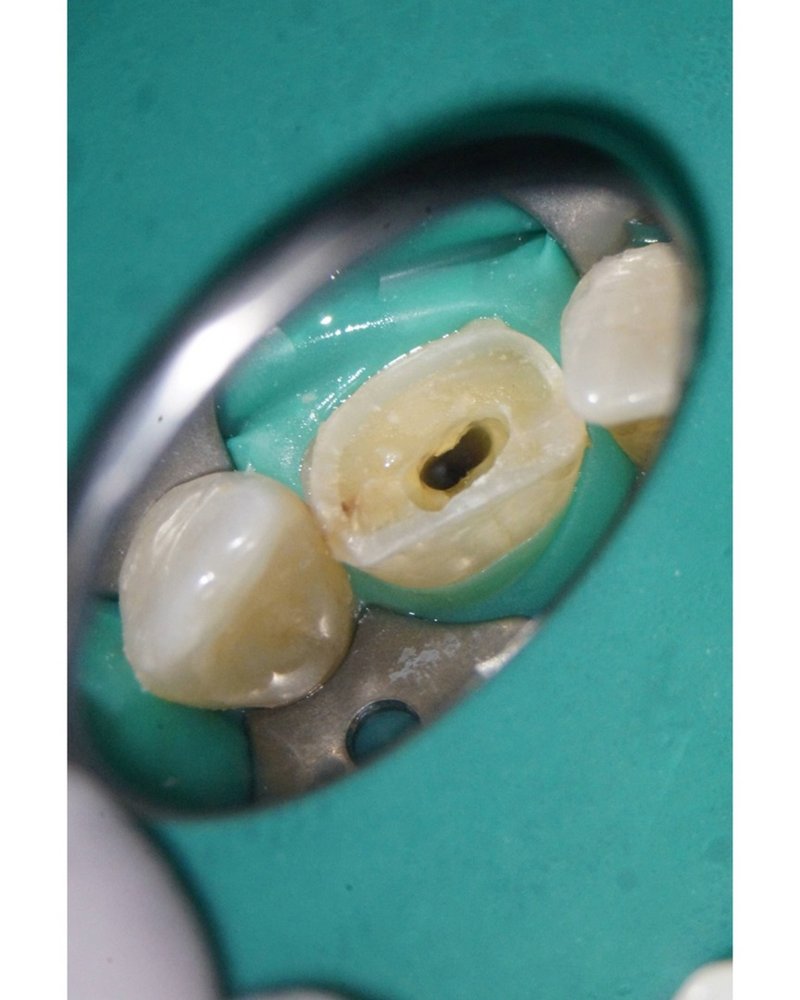

Wurzelkanal unter dem Mikroskop dargestellt